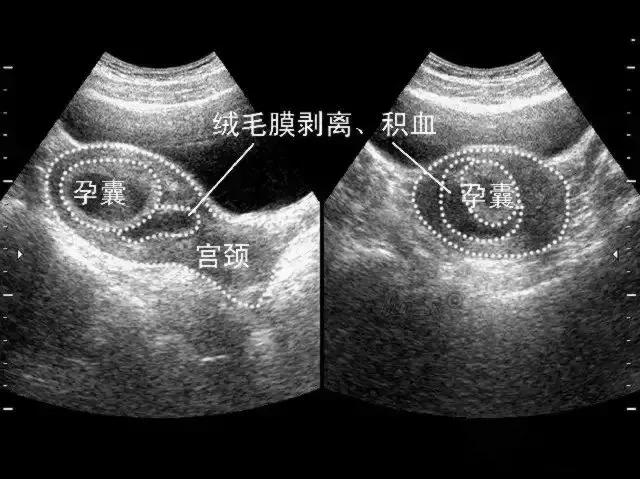

绒毛膜下血肿是指由于绒毛膜与蜕膜之间分离,局部出血积聚而成。不同大小的血肿总是在叶状绒毛膜、平滑绒毛膜与底蛻膜、包蛻膜之间。超声检查可见胎膜与蜕膜部分剥离,其间呈无回声液性暗区,血肿较大有凝血块时其内可见点状、线状或云状高辉度像,轮廓较明显,常位于胎盘下缘,多呈新月状,其血肿下缘常与子宫内口相通,而出现阴道流血。多发生早中孕期。报道的发生率为4%~48%不等。

- 绒毛膜下血肿的超声声像表现为液体集聚在妊娠囊与子宫壁之间,可呈新月形、圆形等多种形状,液体外形取决于子宫的形态变化。血肿局部多普勒检测不到血流信号。